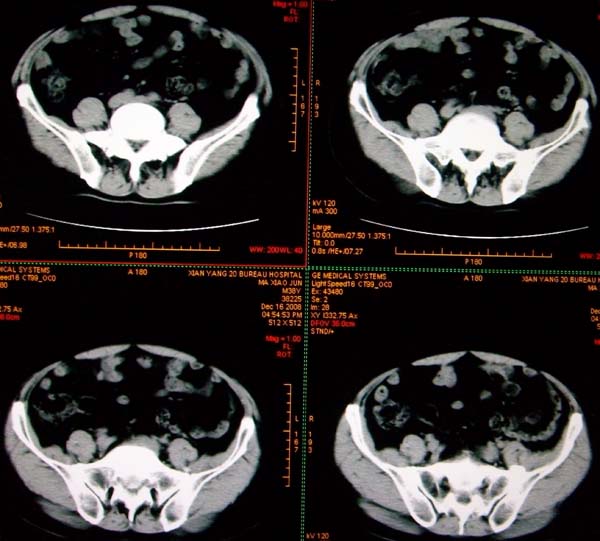

标题: CT17174:M38Y,体检超声提示右肾发育不良,病人无明显不适 [打印本页]

标题: CT17174:M38Y,体检超声提示右肾发育不良,病人无明显不适

右肾发育不良;考虑左肾下极血管平滑肌脂肪瘤可能,建议增强。

1)左肾下极占位性病变,不排除肾癌可能;建议行进一步检查。2)右肾发育不良。

左肾下极占位性病变,不排除肾癌可能;建议增强及明确内部组织ct值。右肾发育不良。

右肾发育不良。左肾代偿。左肾下极占位,性质待定,建议强化。

右肾发育不良。左肾下极囊实性占位,建议增强。